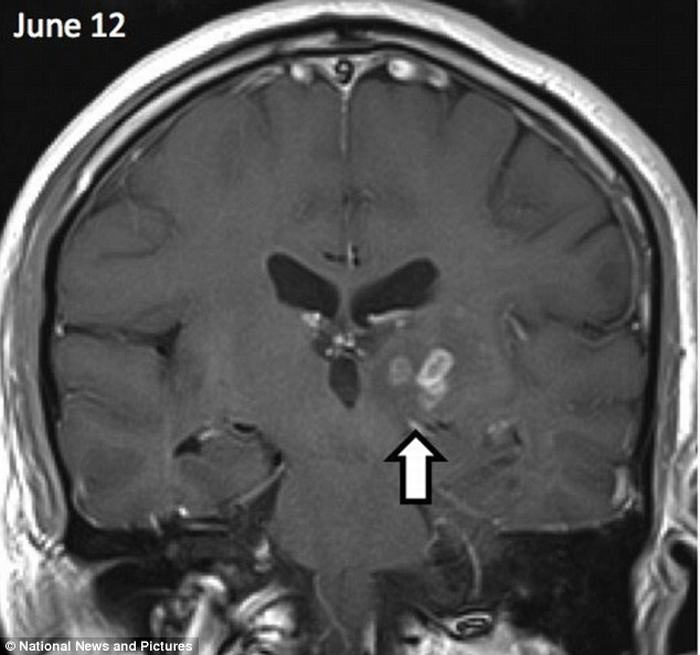

| Con sán đã ‘du lịch’ khoảng 5cm từ phía bên phải sang bên trái của não người đàn ông này trong suốt 4 năm. |

| Đây là loài sán nhỏ xíu được biết đến với tên khoa học Spirometra erinaceieuropaei, thường tìm thấy trong các động vật lưỡng cư và giáp xác ở Trung Quốc. |

| Đây là trường hợp đầu tiên tại Anh và cực kỳ hiếm, vì chỉ có 300 trường hợp được ghi nhận trên thế giới kể từ năm 1953. |

| Khi bị ký sinh, nó gây ra tình trạng viêm các mô gây co giật, mất trí nhớ và đau đầu nghiêm trọng. |

| Nguyên nhân bị nhiễm loài sán này có thể do người đàn ông này đã vô tình ăn động vật giáp xác nhỏ bị nhiễm bệnh hoặc ăn thịt sống từ các loài bò sát và lưỡng cư. |

| Người đàn ông này đã được phẫu thuật loại bỏ con sán. Nếu không, nó có thể đẻ trứng, sau đó ăn hết não để sinh trưởng. |